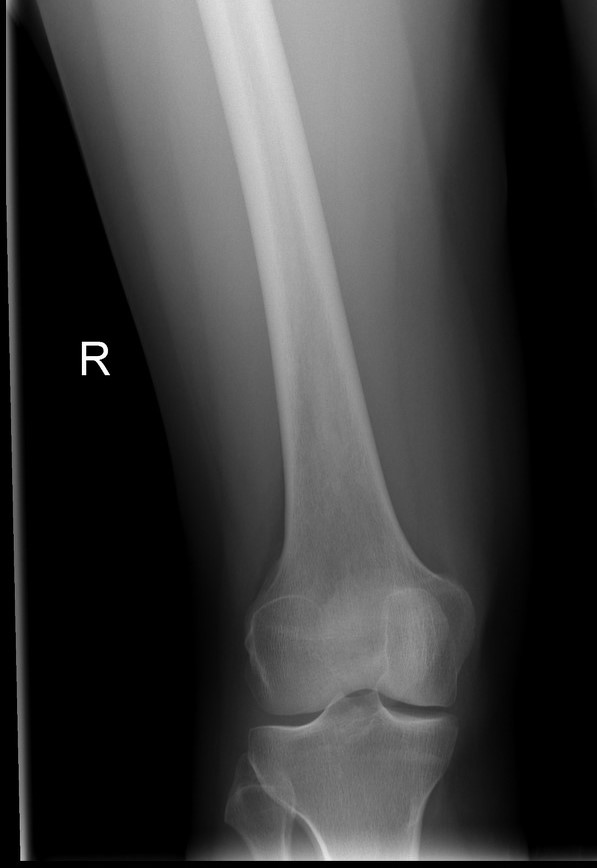

When my daughter was a teenager, the day before starting her freshman year of high school, she fractured her femur while playing on a trampoline in our neighbor’s yard. It was also right before she was to start dance lessons, which was a dream she was finally ready to fulfill. After a long night in the ER, the surgeon decided not to operate and to try to set her bones, realigning them and casting them immobile and allowing her body to do what is designed to do; heal itself. He explained that the recovery rate would take much longer than if he were to put metal bars inside her leg that would allow her to walk on it with full weight much sooner, and that more extensive physical therapy would be required because of the months of scar tissue that would naturally build up causing a protective web to form around the injury. But he said the longer recovery would produce a leg bone which would become the strongest bone in her body because of the trauma it endured. That if it aligned perfectly we should have no fear of future injury because the healing process would force the body to produce fresh, stronger bone around the injured section.